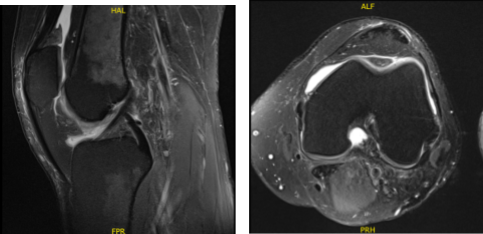

Swelling has decreased. MRI were reviewed and discussed wherein the results have shown 9 x 6 mm full-thickness chondral defect in the midportion of the medial femoral condyle. Focal area of Chondral fissuring and partial-thickness cartilage loss in the central trochlea. Intact medial and lateral meniscus.

MRI-3T Left knee non-contrast